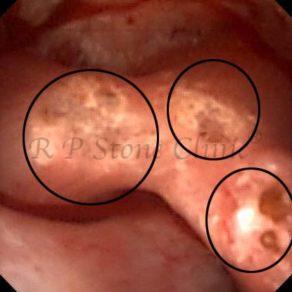

These images are taken as snap shots from the video recording of RIRS Surgery done at our hospital. These are Randall’s Plaques seen with Digital FLEX XC & Digital FLEX XC S. The cream or whitish patches are seen on the tips of RENAL PAPILLAE as seen in images below.

Randall’s Plaques may lead to the formation of Stones.

Those kidney stone patients who have Randall’s Plaques in their kidneys are more likely to form stones again (Recurrent Stones).